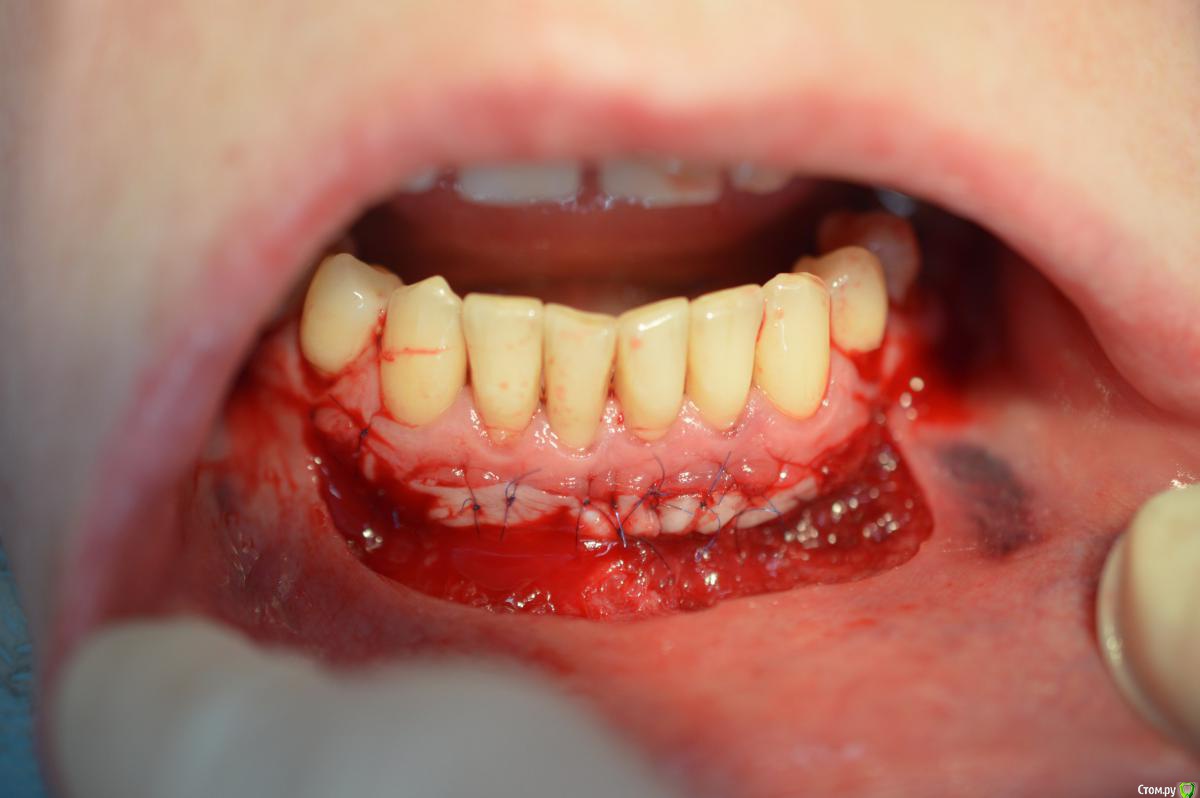

Dr.Safiullin Опубликовано 12 мая, 2017 Поделиться Опубликовано 12 мая, 2017 (изменено) Добрый вечер всем, решил тоже свой первый, небольшой кейс выложитьСильно не ругайте, полгода как получил диплом) Вопрос: 1)Нужно ли подшивать губу? Я не подшил, потому что в гос. времени мало на приём, да и испугался надкостницу травмировать лишний раз. А то боялся получить рубец, хотя не получил его!) 2) на 5 фотке это десквамация? Приветствуются конструктивная критика! Спасибо Изменено 12 мая, 2017 пользователем Dr.Safiullin Ссылка на комментарий

колесников Опубликовано 13 мая, 2017 Поделиться Опубликовано 13 мая, 2017 (изменено) Прелестное было преддверие. Обратить внимание следовало на особенности прикуса, выявить в анамнезе бруксизм, местно -суперконтакты. Думаю причина рецессии в перегрузке.Кстати подшивать лоскут надо было к кератинизированой слизистой,тогда не было бы диссонанса в цвете в виде зебры ,в окончательном варианте Изменено 13 мая, 2017 пользователем колесников Ссылка на комментарий